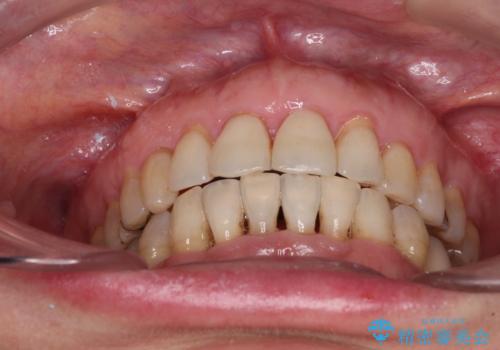

口元の出っ張りとデコボコを改善したい

- 近医にてインプラント治療を行った後に矯正治療を希望され、来院された患者様です。

口元の突出感とデコボコが気になっているとのことでしたが、インプラントが既に3本埋入されていたため、抜歯矯正による口元を引っ込めることができない状況でした。

近医での歯周病治療の影響でブラックトライアングルが発現していたため、IPR(歯と歯の間を削る)で隙間を改善しつつ、インプラントを固定源に歯列全体を後方へ移動させることとしました。